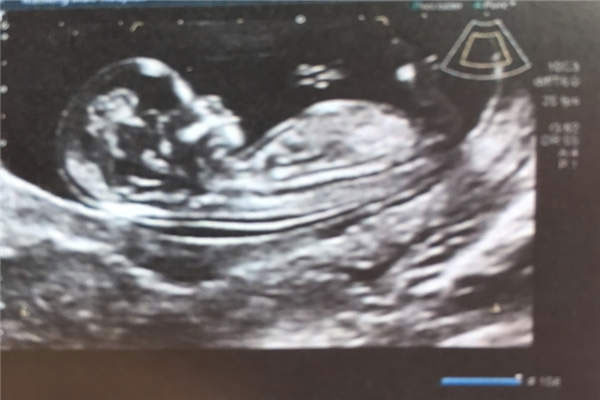

孕11周nt女孩图

网传怀女孩的nt图都是平行的,胎儿宝宝的姿势是平缓的躺在妈妈的肚子里,双腿没有往上翘,脊柱线也没有弯着。网上总结的nt图卡男女结论是,如果nt图弯着的男孩居多,nt图平行的女孩居多,这个结论可以通过胎儿的脊柱线来佐证。据称,如果脊柱线到尾椎骨链接是小于30度的话,则为女孩。

据已验证的宝妈分析来看,如果怀的是女孩,胎儿的双腿也不会往上翘,如果是男孩的话这里是会往上翘的,因为男孩后面还要发育外生殖器官,也就是小JJ和睾丸,所以说这里才会翘起来,而女孩的则不会,而正因为如此才有男孩nt图弯着的,女孩nt图平行这样的说法。要这样看的话好像也不无力道理,但不管是nt图也好也还是其他的方法也好,都无法保证100%的,大家自行参考哦。